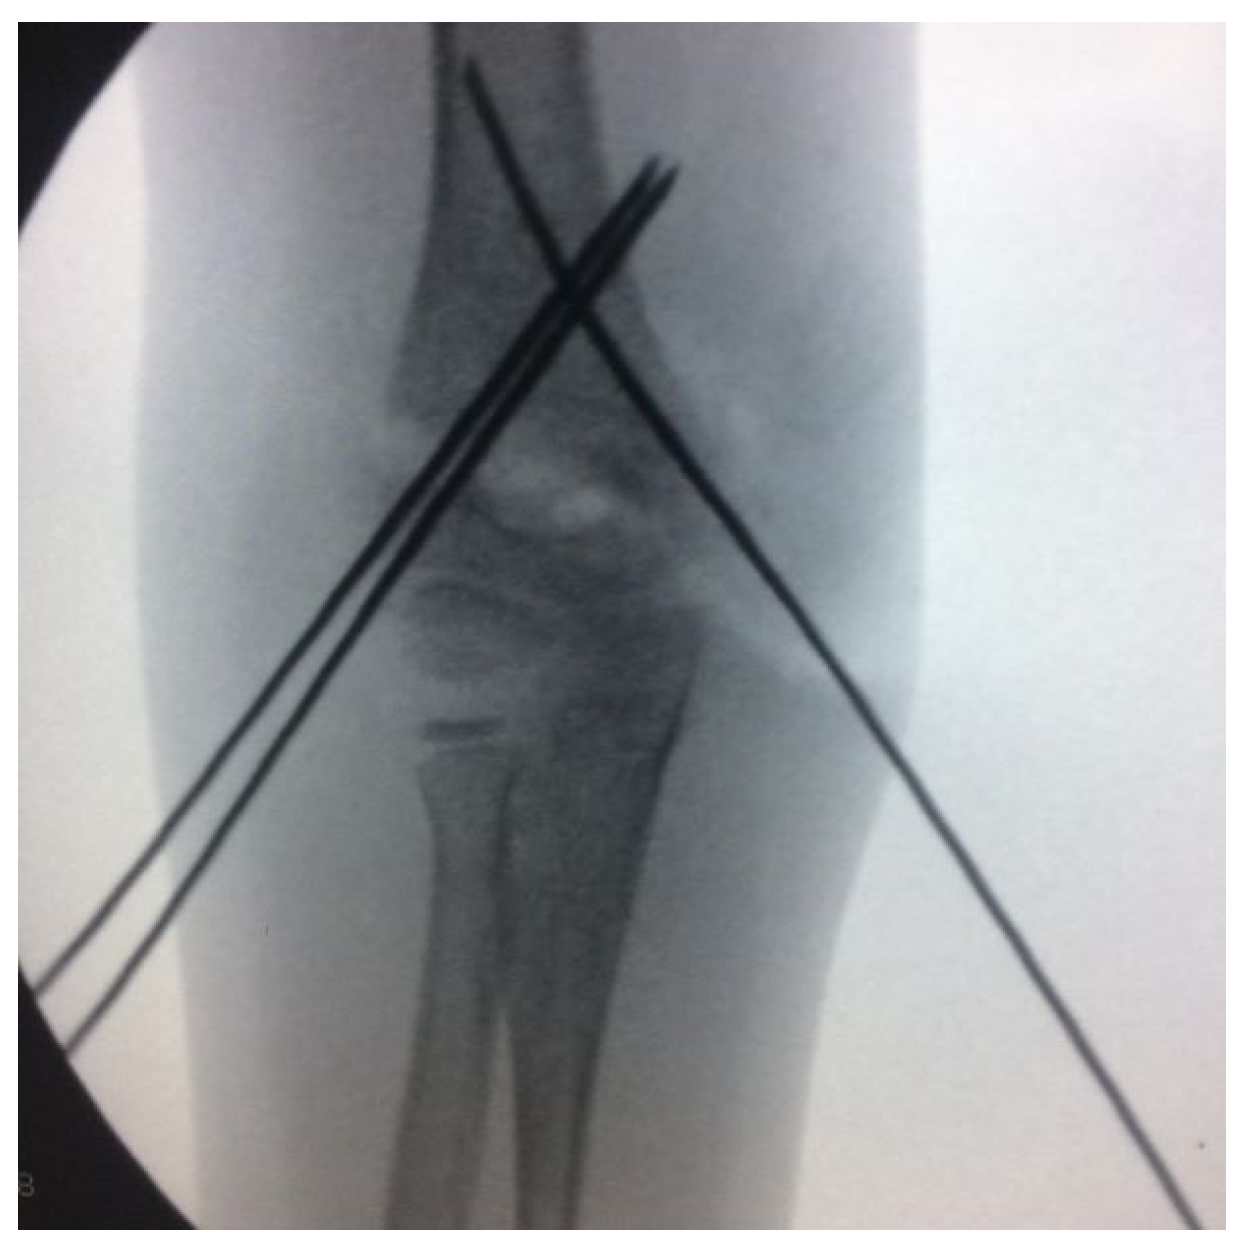

Extra Lateral Pin or Less Radiation? A Comparison of Two Different Pin Configurations in the Treatment of Supracondylar Humerus Fracture

2. Materials and Methods